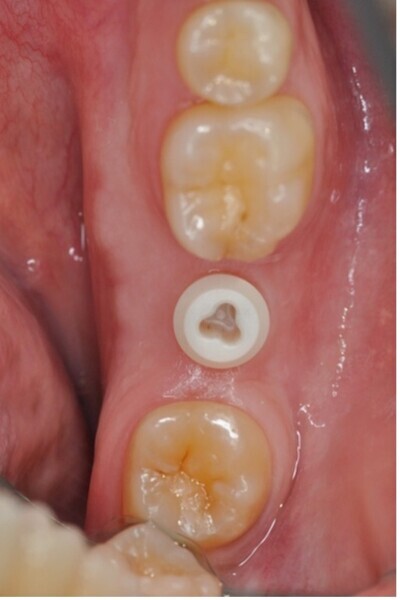

Accumulation de particules métalliques dans les tissus péri-implantaire

Fig. 2 : Particules métalliques retrouvés dans les tissus mous et l’os, d’un site où un implant atteint de péri-implantite a été retiré.

Les microparticules de Ti relarguées par les implants dentaires en raison de la bio-tribocorrosion peuvent s’accumuler dans les tissus locaux.40, 41 Ces phénomènes constituent localement un facteur de risque des péri-implantites et peuvent potentiellement poser d’importants troubles de santé. Le taux de Ti dans le corps ne devrait pas dépasser 15 mg par 70 kg de poids corporel chez un individu en bonne santé.40 Ces concentrations durent de quelques heures à plusieurs mois car le Ti est très insoluble et difficilement éliminé de l’organisme.40, 42, 43 Les particules de Ti détruisent l’homéostasie intra-épithéliale de la bouche, favorisent l’inflammation des tissus péri-implantaires et affectent les ostéoblastes et les ostéoclastes, ce qui entraîne une perte osseuse autour des implants.40

Les ions Ti augmentent la sensibilité des cellules épithéliales gingivales aux micro-organismes et favorisent l’infiltration des monocytes dans la cavité buccale, ce qui entraîne une cytotoxicité et une inflammation à l’interface entre l’implant et le tissu gingival.44

Il a été remarqué la présence de particules Ti de 1 à 10 μm de diamètre libérées lors de l’élimination de biofilm autour des implants dentaire (Fig. 2). Ces particules sont cytotoxiques pour les fibroblastes.45